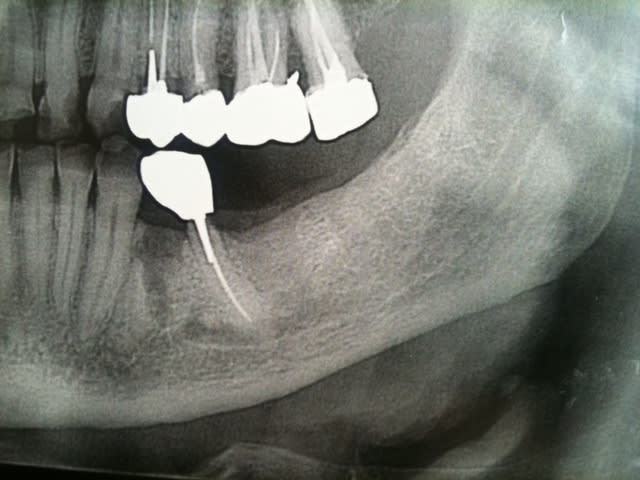

un avis implantaire pour mon premier implant au niveau d'une 36 extr faite en sept 2009

quelle longueur environ? je pensais a un 4/10mm ...

un scanner est il indispensable dans ce cas ?

Ps extr delicate et os tres corticalisé...

derniere radio faite avec angulateur .... et en mars 2010

la crete est tres large et peu de concavite en L.

c'est juste la longeur qui m'inquiete

le cone apres extr dans l'alveole mesure 19 mm et avec la radio je mesure 18 mm : il y a peu de deformation